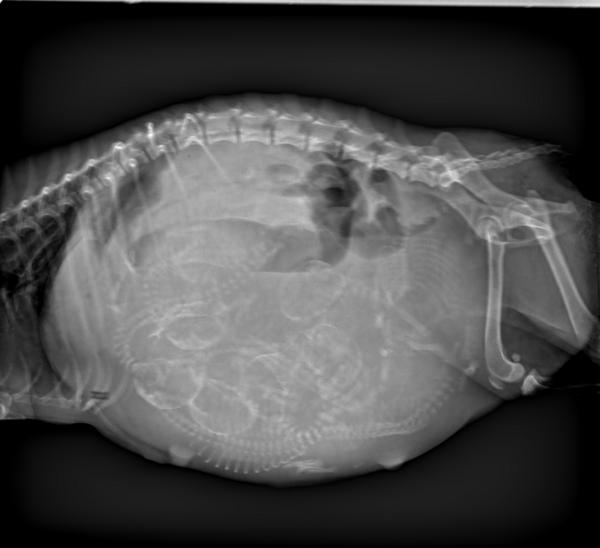

DR显示

6个胎儿胎位不正后脚朝下

DR显示有可能两个胎儿堵在阴道上端,